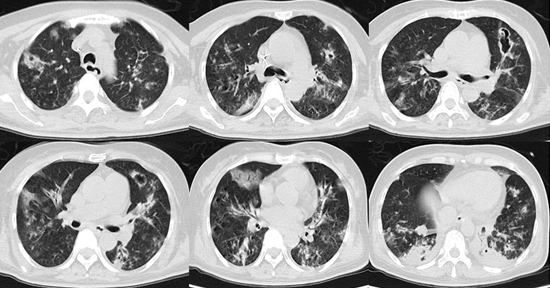

影像学(20181月31):沿支气管血管束分布的斑片影,部分出现空洞,胸膜下实变影。

图片

根据患者早期症状和检查结果,启动了经验性抗真菌治疗。根据3天后回报的BALF GM试验阳性结果诊断为IAA。抗真菌治疗2周后,复查胸部CT可见病灶较前明显吸收,最终患者康复出院。我们总结此例患者治疗有效的经验,是早期即根据患者症状、实验室检查和影像学表现诊断了IAA,缩短了患者从起病至治疗的时间。